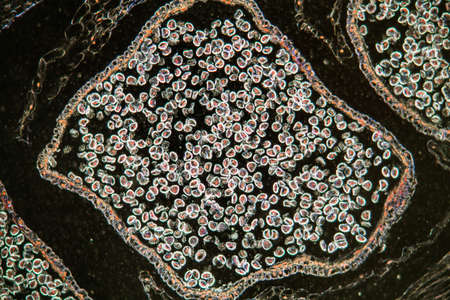

Bowen's Disease Tumor under the microscope 100x

Bowen's Disease Tumor under the microscope 100x